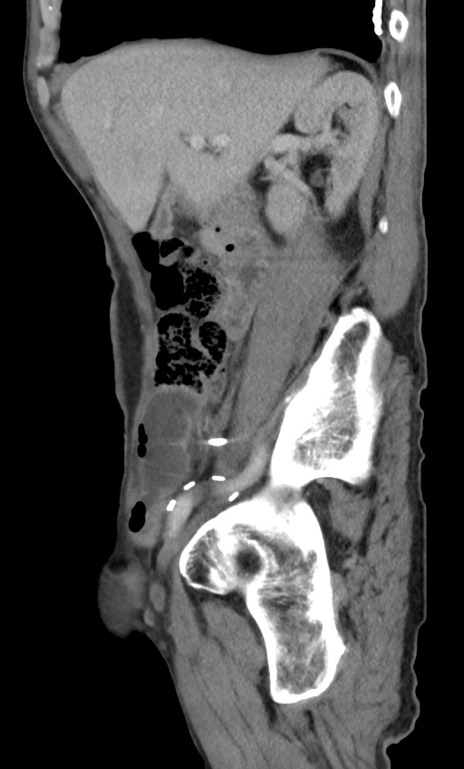

症例3(矢状断像)

【症例】 70歳代男性

【主訴】右鼠径部腫瘤、疼痛

【現病歴】本日朝より上記主訴あり、受診。

【既往歴】膀胱癌にて膀胱全摘、両側尿管皮膚瘻

【データ】WBC 5600、CRP 0.56